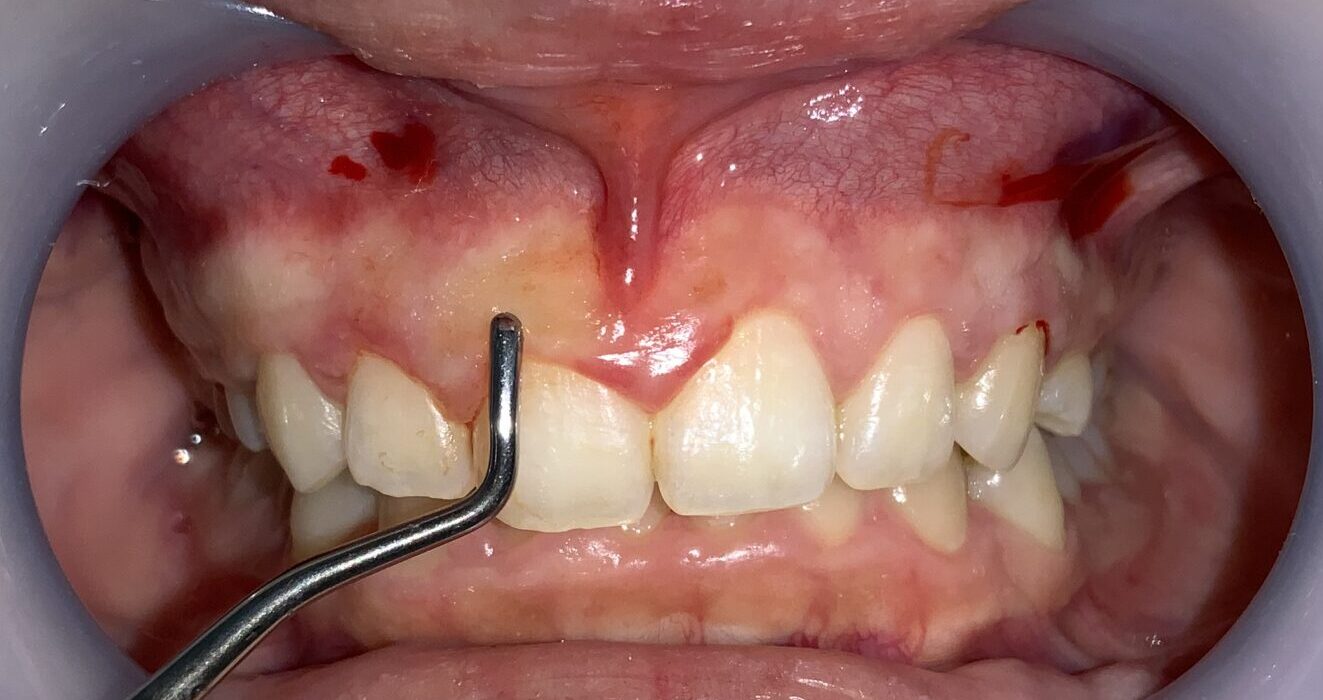

さらに隣の歯も検査します。

こちらの歯は犬歯です。大きく切り取り過ると、八重歯になってしまうので、注意が必要です。

安全に切除できる範囲の歯ぐきを計測します。

反対側の歯の検査に移動します。

歯ぐきの厚みや歯槽骨の状態も確認します。

この歯も歯ぐきが被っている量が相当あります。

最後に犬歯の検査をします。

犬歯もこのように小さな形ではなく、綺麗な形になります。

八重歯にならないように細心の注意をします。